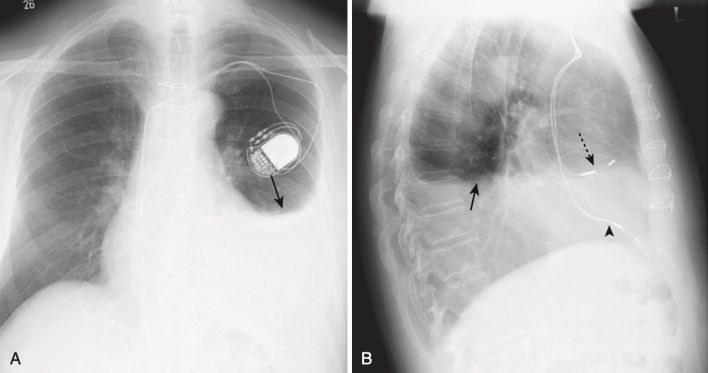

- Hội chứng Dressler (Box 1, Hình 1)

| Box 1 HỘI CHỨNG DRESSLER |

|---|

| Còn được gọi là hội chứng sau phẫu thuật cắt màng tim / sau nhồi máu cơ tim. Thường xảy ra từ 2 đến 3 tuần sau nhồi máu cơ tim xuyên thành, gây tràn dịch màng phổi trái, tràn dịch màng ngoài tim và bệnh vùng khoảng chứa khí từng đám ở đáy phổi trái. Kèm với đau ngực và sốt, nó thường đáp ứng với aspirin hoặc steroid liều cao. |